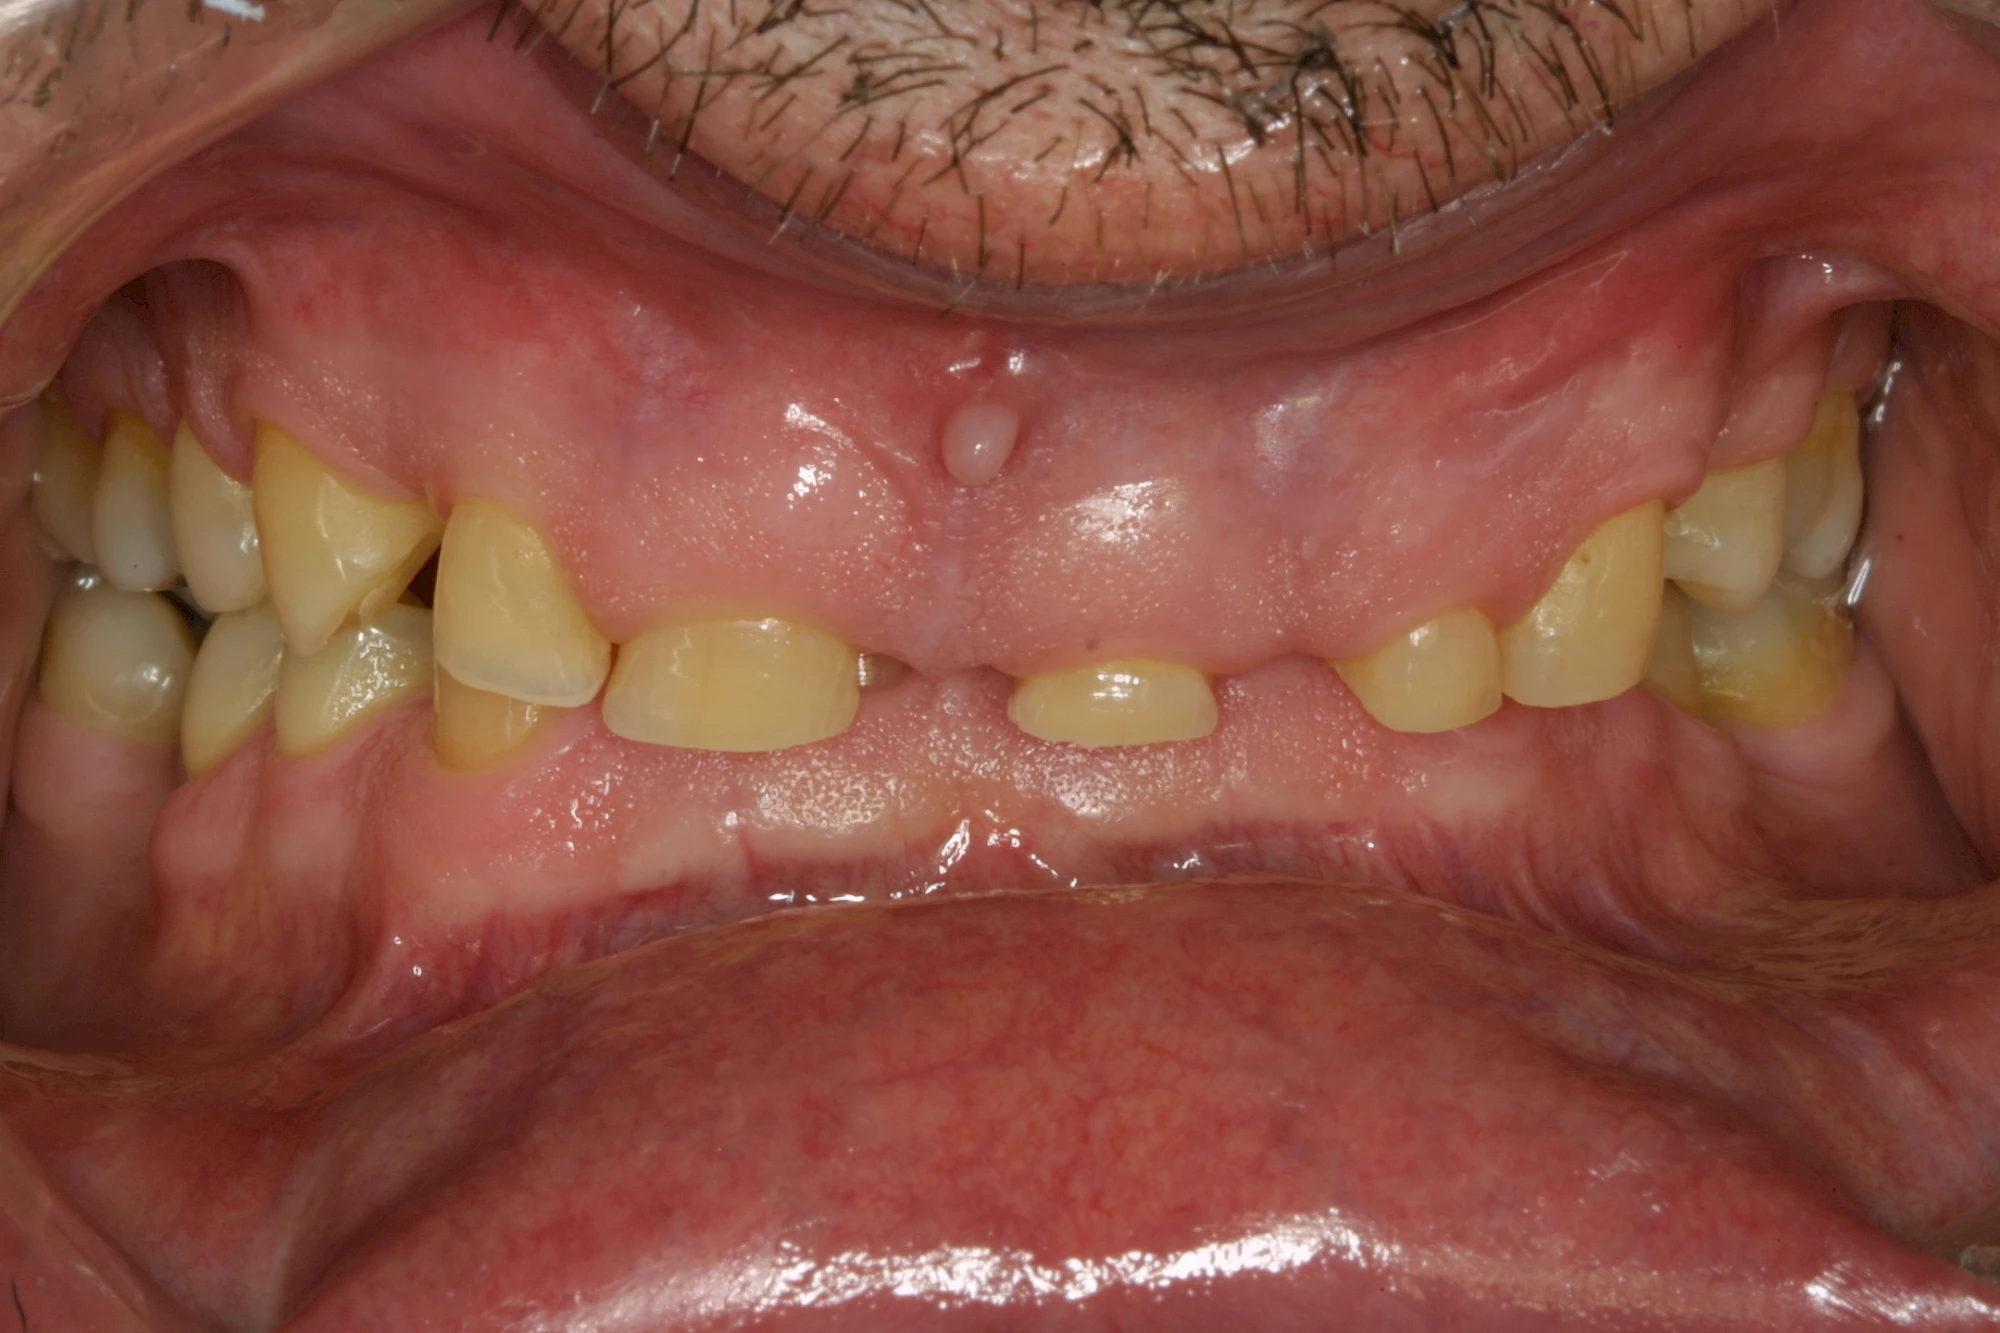

- Abnutzung durch Kauen (Abrasion) oder duch durch übermäßiges Knirschen bzw. Pressen (Attrition)

Die Zähne können dabei auf Reize (warm, kalt, süß, sauer) oder auch beim Zähneputzen empfindlich oder schmerzhaft sein. In allen diesen Fällen ist es sinnvoll, den Zahnarzt zu kontaktieren und das weitere Vorgehen abzustimmen.

Auswaschung (Erosion) dagegen ist eine Verschleißerscheinung der Zähne aufgrund von immer wiederkehrenden Säureangriffen durch die Nahrung, verstärkt zum Beispiel durch den Genuss säurehaltiger Getränke oder Speisen. Auch bei Menschen mit einer Essstörung (z. B. Bulimie) können die Zähne durch die Magensäure ausgewaschen erscheinen.